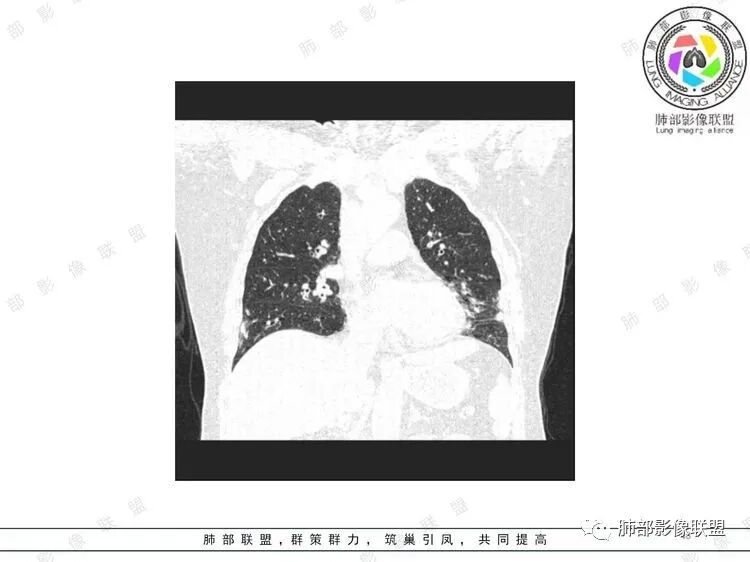

胸CT:双中下肺支气管壁明显增厚,双下肺胸膜下可见实变区。部分病变呈楔形影。

双肺支气管管壁弥漫性增厚,管腔狭窄,下叶为主,伴多发高密度结节影,边缘模糊,双肺支气管血管束明显增粗,临床症状咳嗽低热,有血尿,首先考虑血管炎

影像上:多发结节沿血管分布;双下叶支气管血管束简直增厚,偏血管,支气管通畅

膀胱炎症

肠系膜血管周围有渗出

左上颌窦粘膜下囊肿,鼻甲肥厚

右肾结石

累及范围广泛:肠系膜血管?膀胱